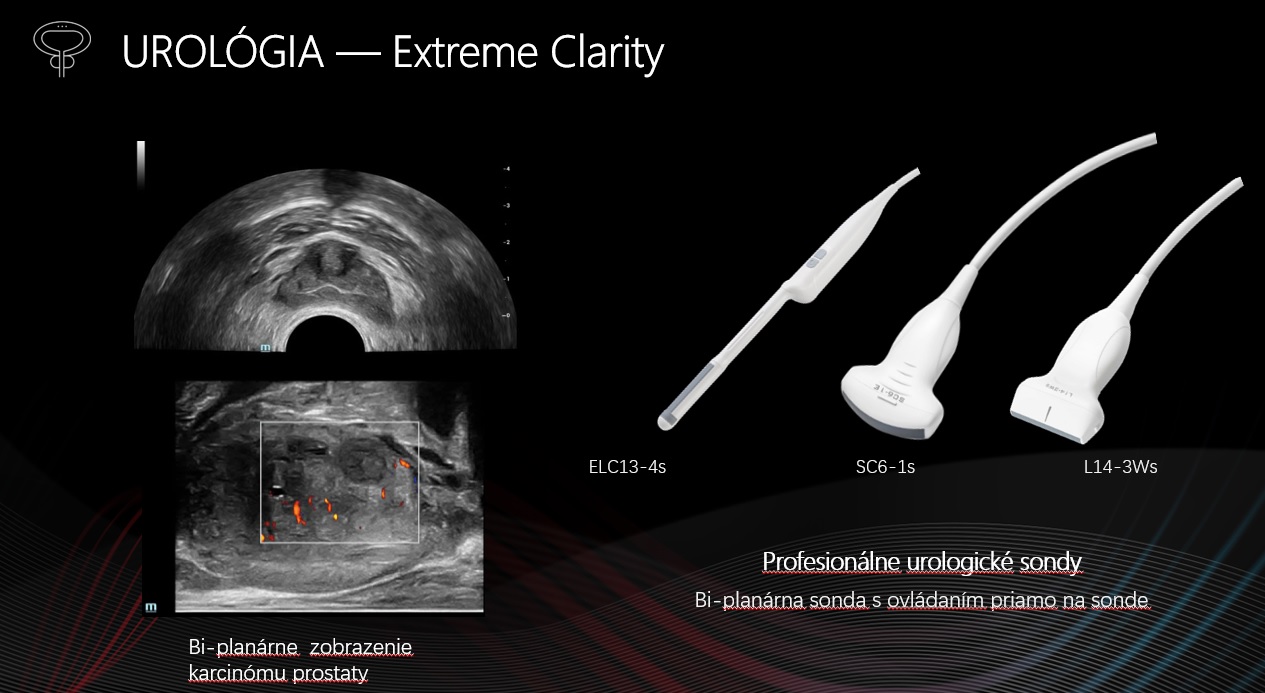

Profesionálne urologické sondy : ELC13-4s, SC6-1s,L14-3Ws. Biplanárna sonda s tlačidlami.

Elastografia prostaty

Natural Touch Elastografia, Strain Elastografia

Sound Touch Elastografia

Vyhodnotenie tuhosti prostaty pre lepšiu diagnostiku rakoviny prostaty.

CEUS prostaty

Vyhodnotenie perfúzie mikrocirkulácie na diagnostiku rakoviny prostaty. Technológia UWN+, vysoká citlivosť, dlhá doby perfúzie.

iFusion* prostaty

Fúzia UZV obrazu s CT alebo MRI zobrazením. Citlivejší magnetický snímač pohybu s milimetrovou presnosťou. Vďaka CT/MR navigácie poskytuje presnú lokalizáciu nádoru ako aj lepšie vedenie intervencie.